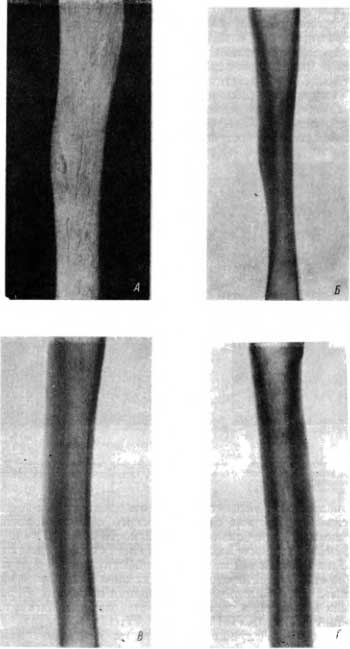

Типичная саблеобразная деформация обеих большеберцовых костей в результате сифилитического остеопериостита была обнаружена нами у скифа эпохи бронзы из Забайкалья (раскопки Г. П. Сосновского). На рис. 35 представлена рентгенограмма правой большеберцовой кости. Аналогичные сифилитические изменения наблюдались и на левой большеберцовой кости.

Рис. 35. Саблеобразная деформация большеберцовой кости в результате сифилитического остеопериостита.

Сифилитические поражения длинных трубчатых костей были представлены специфическим оститом и периоститом различной протяженности, неравномерно утолщающим диафиз трубчатых костей.

Из длинных трубчатых костей чаще всего были поражены большеберцовые кости, отличающиеся характерными изменениями в области переднего гребня, который был равномерно или неравномерно утолщен и дугообразно искривлен выпуклостью кпереди. На рентгенограммах этих большеберцовых костей определялось резкое утолщение переднего кортикального слоя диафиза; он намного превосходил в этом отношении ширину костномозговых пространств на соответствующем уровне, что типично для сифилитического остеопериостита. Кости предплечья были неравномерно утолщены за счет периостальных наслоений и сопровождавшего их эностального склероза.

На правой большеберцовой кости мужчины, на внутренней поверхности диафиза кости в средней ее трети у переднего гребня, хорошо видна окостеневшая сифилитическая гумма (рис. 37, А). Вся поверхность диафиза этой кости лишена обычной гладкости, она как бы расслоена. Передний гребень в области окостеневшей гуммы утолщен.

Рис. 37. А — окостеневшая сифилитическая гумма на переднем гребне большеберцовой кости, поверхность кости изменена благодаря окостеневшим периостальным наслоениям; Б — резко выраженный остеопериостнт в области, соответствующей расположению окостеневшей гуммы; В, Г — сифилитический остеопериостнт большеберцовой кости.

На рентгенограмме с этой большеберцовой кости хорошо виден сифилитический остеопериостит, захватывающий среднюю треть диафиза. Передний кортикальный слой в наиболее измененном участке почти в 3 раза толще заднего кортикального слоя (рис. 37, Б). Костномозговые пространства в средней трети диафиза резко сужены в результате склерозирования спонгиозных участков, примыкающих к переднему кортикальному слою. На уровне расположения окостеневшей гуммы утолщение кортикального слоя особенно резко выражено (рис. 37, Б).

Остеопериостит (рис. 37, В) был обнаружен на правой большеберцовой кости. Костномозговые пространства в средней трети диафиза резко сужены и располагаются эксцентрично по отношению к оси кости. Сходная рентгенологическая картина сифилитического остеопериостита была обнаружена еще на одной большеберцовой кости (рис. 37, Г).